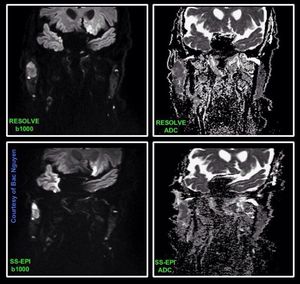

Read-out Segmented Echo-Planar Imaging (RS-EPI) is a revolutionary new approach for obtaining high-quality, high-resolution DW images even in body regions strongly affected by susceptibility artifacts, such as head/neck. Images courtesy of Bac Nguyen.